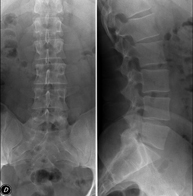

Tècnica que usa els raigs X a través de la qual s'obtenen imatges de l'abdomen (estómac, intestí prim, intestí gros, fetge, ronyons, bufeta, pelvis òssia, etc.) per al seu estudi. - RX Columna lumbar

Tècnica que usa els raigs X a través de la qual s'obtenen imatges de la columna lumbar per al seu estudi. - TEGD (trànsit esòfag-gastro-duodenal)

- Lumbar spine X-ray

This technique uses X-ray rendered imaging to examine the lumbar spine. Indicated for: sciatica, trauma, lower back pain.

- Spinal teleradiology

This technique uses X-ray rendered imaging to examine the entire spinal column, especially assessing the presence of scoliosis and pelvic dysmetria.